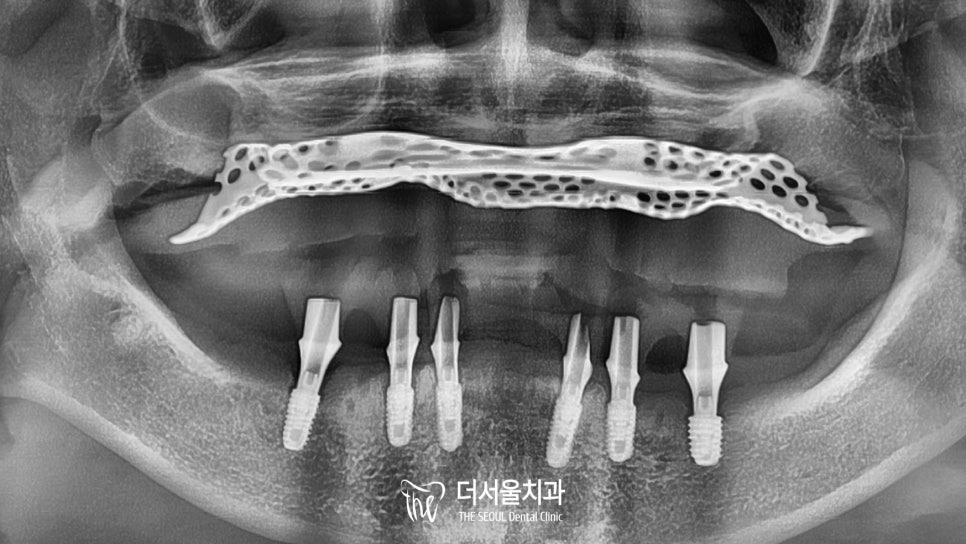

이분께서는 오랜 기간 틀니를 쓰고 있었으며,

구강 내 치주 질환으로 치조골 소실이 심하게 나타나 있었는데요.

그렇다면 뭐죠?

골. 이. 식. 을 통해 모자란 골의 양을

충분히 채워준 뒤에 진행을 해야 된다는 사실!

발치 즉시 골이식(GBR)를 해서

단단히 심어질 수 있도록 도와드려야겠네요.

최종 보철 제작까지 미리 고려하여

픽스처의 방향, 각도를 설정해 주었습니다.